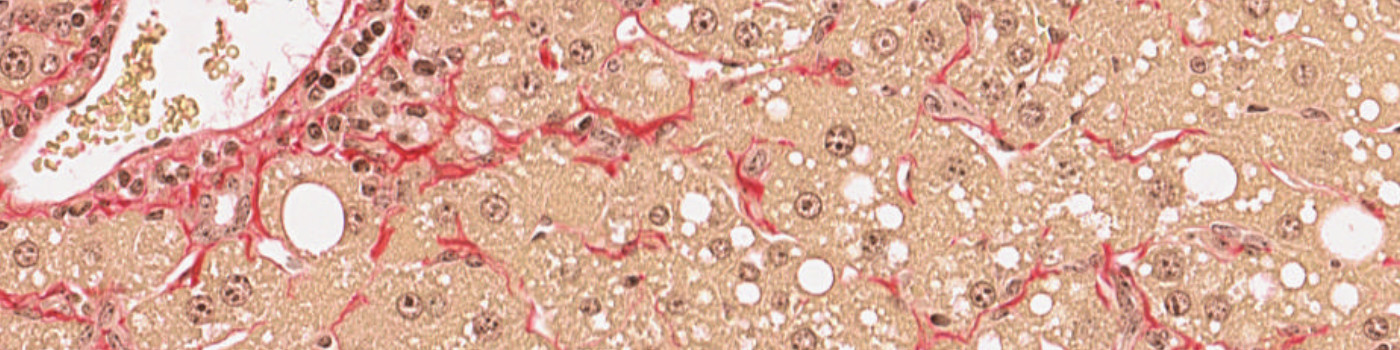

Figure 5

PSR stained liver tissue with fibrosis.

Figure 6

PSR stained liver tissue with identified fibrosis. Fibrosis in the perisinusoidal space is shown in green and the fibrosis in the periportal space is shown in turquoise.